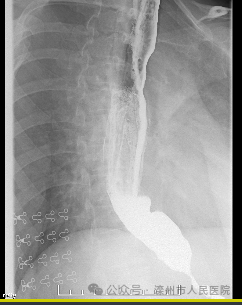

近日,滦州市人民医院消化科成功开展了首例内镜下贲门失弛缓肌切开术(POEM),成功解除了患者长达十年的吞咽痛苦,术后症状...